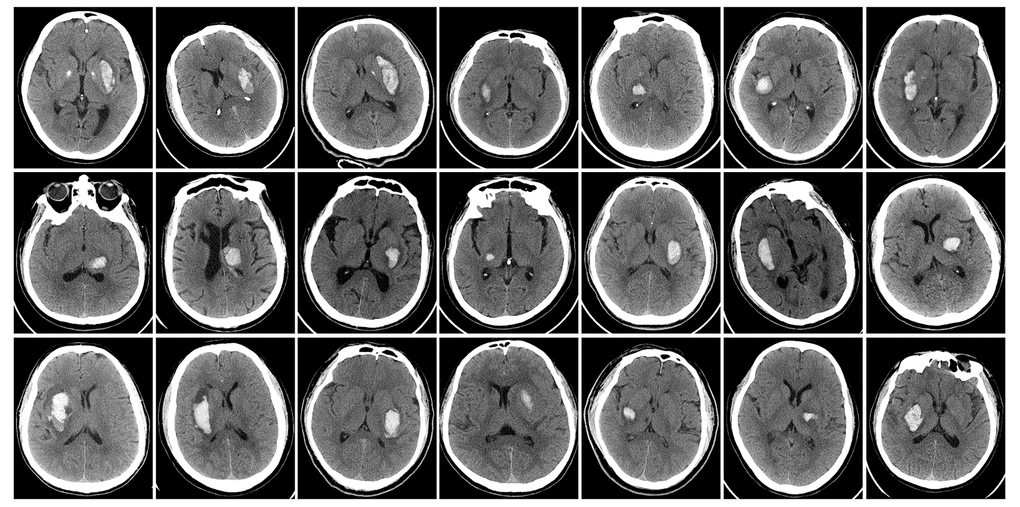

The Ethics Committee of the Clinical Medical College of Yangzhou University approved this study, and written informed consent was obtained from each subject. ICH patients hospitalized in the Department of Neurology and undergoing medical therapy were consecutively enrolled between June 2016 and December 2016. Inclusion and exclusion criteria are listed in Table 3. Single deep supratentorial intracerebral hemorrhage, including in the basal ganglia and thalamus, was diagnosed by CT (Figure 7). A total of 21 ICH patients were included (among which 16 were male); the mean age was 59.29 ± 9.89 years (range from 45-75). Ten healthy volunteers matched in age, sex and education level were recruited as a control group.

Figure 7. Baseline head CT of ICH patients immediately after admitting hospital.